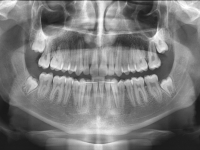

El paciente E.A. acude a nuestra consulta por diastema inferior y ausencia de contactos en los sectores laterales.

El stripping consiste en la reducción interproximal del esmalte entre los dientes posteriores y anteriores, así obtenemos espacio para alinear los dientes apiñados.

Chica de 17 años tratada en 1 año con stripping en los dientes inferiores